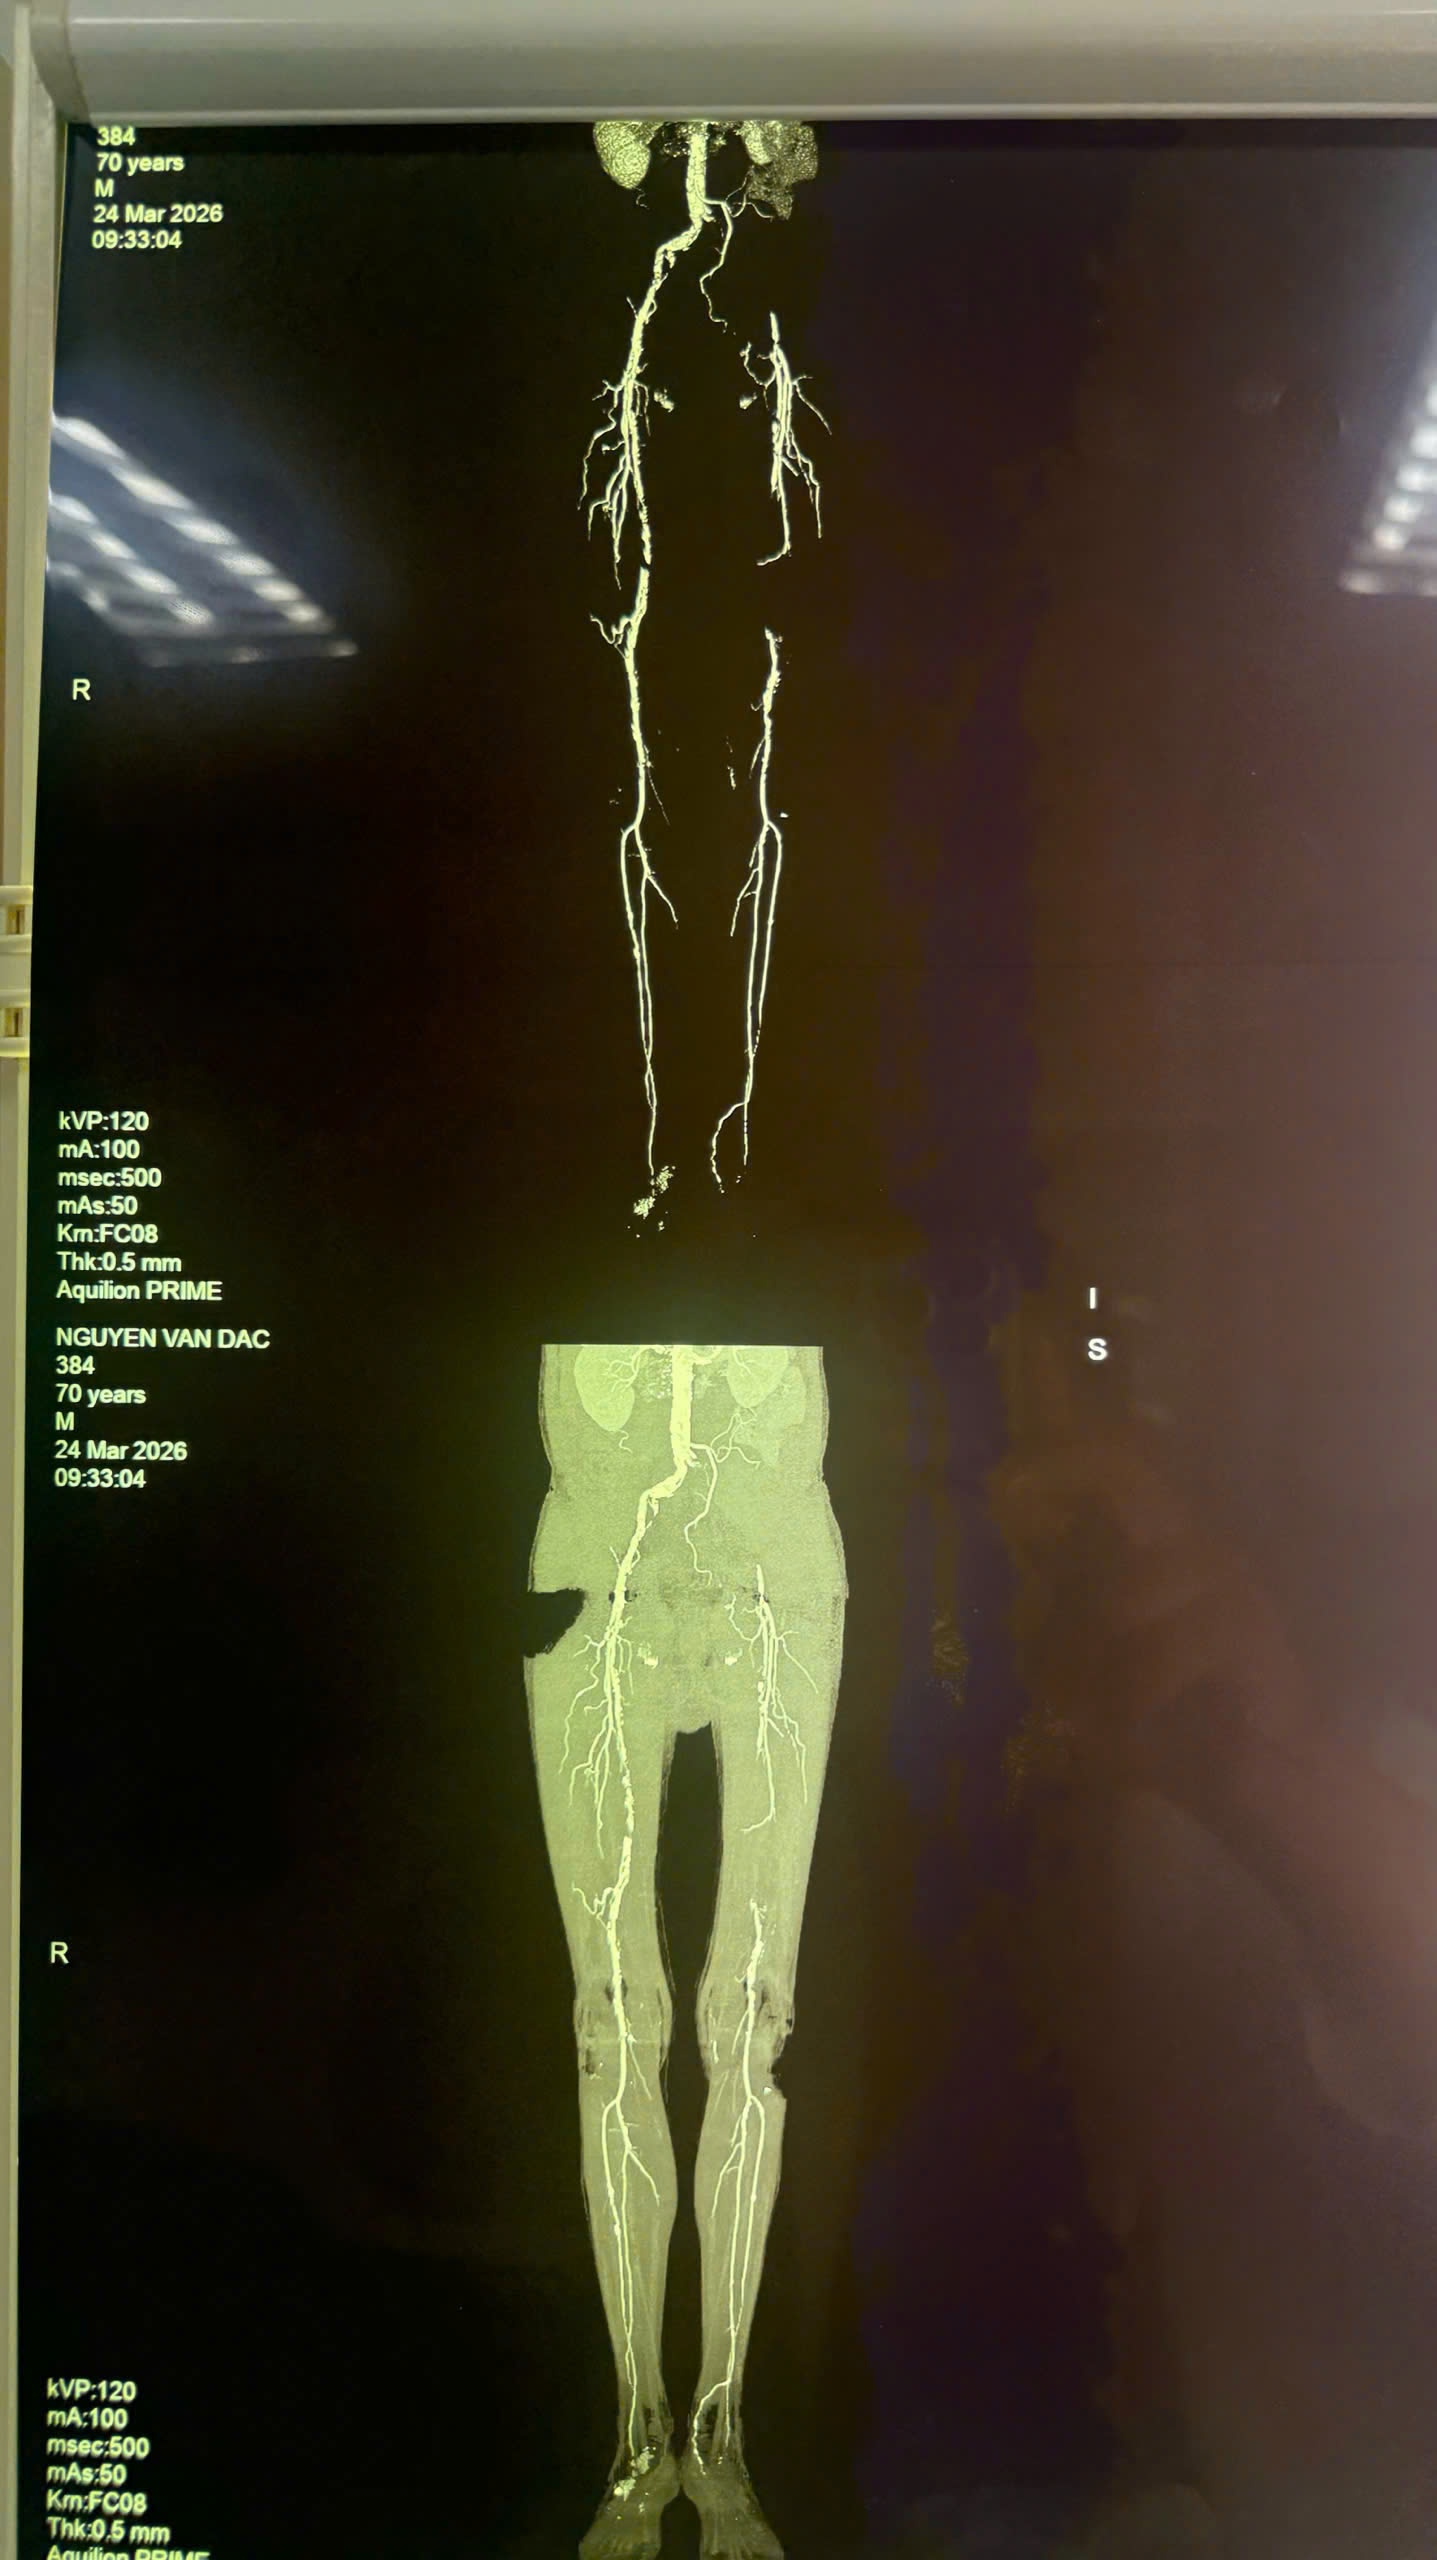

| Hệ thống mạch máu chi dưới của bệnh nhân được dựng hình. |

Qua thăm khám và thực hiện các cận lâm sàng như siêu âm Doppler, chụp cắt lớp vi tính mạch máu (CTA), các bác sĩ xác định bệnh nhân bị tắc động mạch chậu trái, tắc đoạn giữa động mạch đùi trái, kèm xơ vữa nhiều vị trí ở hệ động mạch chi dưới.